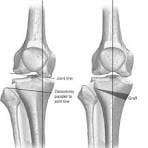

A distal femoral osteotomy involves creating a surgical fracture at the end of the femur and changing the bone’s shape. Usually, people with knocked knees undergo the procedure. It is termed valgus alignment. The surgery intends to realign knees in a way that the weight-bearing axis is changed to pass through the knee’s center or only into the knee’s interior compartment.

A high tibial osteotomy helps realign the knee joint. In patients suffering from knee arthritis, HTO can delay or avoid partial or total knee replacement by preserving the damaged joint tissue. Surgeons usually perform HTO to treat medial, uni-compartmental osteoarthritis of the knee and/or fix misalignment of bones that form the knee joint.